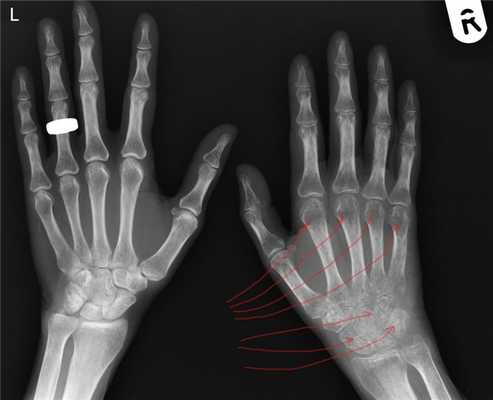

Стадия Зудек I (острая). Характеризуется отсутствием клинических симптомов улучшения (уменьшение боли, гиперемии кожи, уменьшением припухлости, сморщивания кожи т.д.), которые в нормальных условиях появляются уже в конце первой недели после повреждения. Отёк не только не уменьшается, но даже увеличивается, кожа гиперемирована, боли усиливаются, присоединяются неукротимые, не котирующиеся препаратами из группы НПВС - ночные боли. Пациент не может уснуть, как следствие истощение нервной системы на фоне прогрессирующей бессонницы. Боли не уменьшаются ни при иммобилизации (гипсовая, с использованием ортеза при растяжениях и ушибах), ни при поднятом положении конечности. Прикосновение к этому отделу конечности, особенно надавливании на мышцы, вызывает нестерпимую боль. К концу второй недели красный цвет кожи может переходить в синюшный, отмечается атрофия мускулатуры (пальцы «не слушаются, не сгибаются - сильная боль и .т.п.). Активные движения в суставах кисти резко ограничены, болезненны. На четвертой недели рентгенограмма костей кисти с захватом лучезапястного сустава показывает неравномерное затенение (на рентгене как просветление). Если имеется рентгенограмма обеих кистей и предплечья, то признаки остеопороза наиболее рано выявляются в дистальных эпифизах пястный костей.

Стадия Зудек II (дистрофия). Боли в кисти держатся и не проходят. Суставы неподвижны, попытки пассивного (самостоятельно здоровой рукой двигать пальцы больной кисти) движения вызывают резкое усиление постоянно нестерпимой боли. Кожа цианотичная, на ощупь холодная, часто отмечается сильное потоотделение (ладонь больной кисти мокрая от пота). На рентгенограмме неравномерное затенение выражено не так ясно, как в 1-й стадии. Рисунок принимает облачный характер, балочки губчатой кости исчезают, корковый слой суживается. Контуры кости выявляются так ясно, как будто бы они очернены карандашом.

Стадия Зудек III (атрофия). В отдельных, далеко запущенных случаях и при крайне позднем обращении за квалифицированным этиотропным лечением, несмотря на предпринятые меры, патологический процесс не улучшается и в течение полутора-двух лет, от момента заболевания или травмы, доходит до конечной стадии. Кисть атрофична, холодная, суставы неподвижны. Ногти четко показывают трофические расстройства. Боли полностью прекращаются. Дифференцированные скользящие ткани кисти замещаются соединительной тканью (кисть как в панцире-перчатке, кожа в складки на тыле при защипывании не собирается). В этой стадии на рентгенограмме выявляется бедность костей известью, и помимо этого хорошо видны балки губчатой кости (крайне выраженная картина «тигрового» остеопороза).